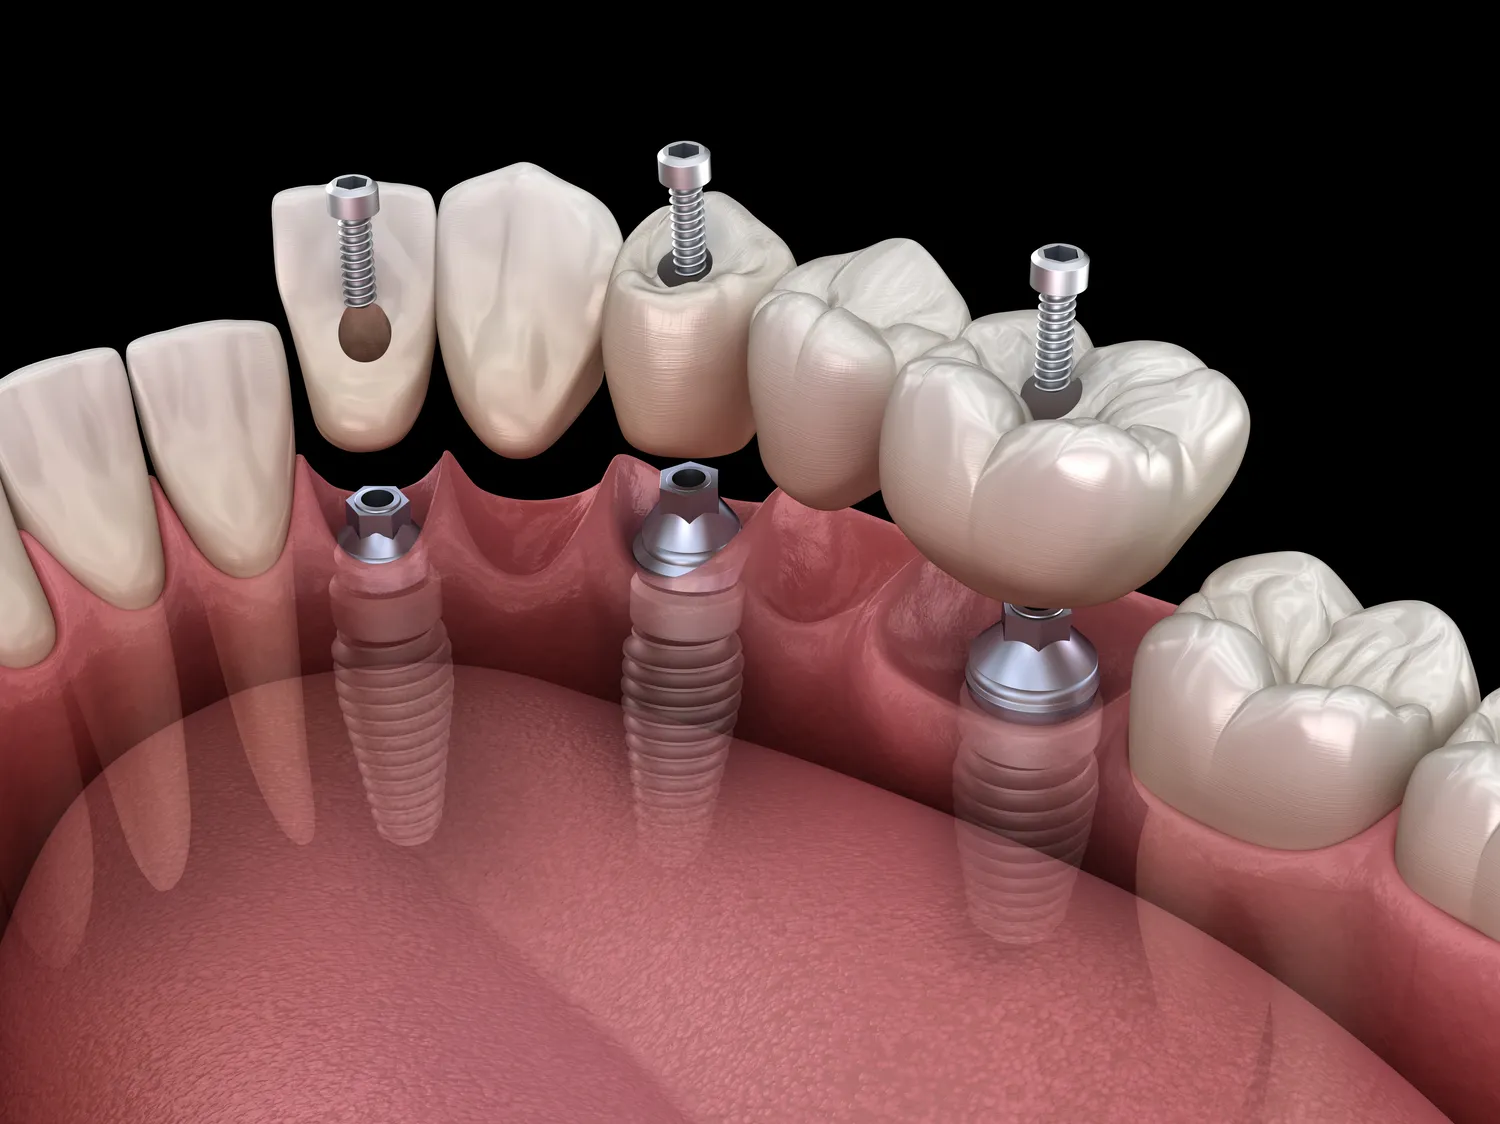

Jakie są alternatywy dla leczenia kanałowego

Leczenie kanałowe jest skuteczną metodą ratowania zębów, jednak nie zawsze jest jedyną opcją. W przypadku, gdy ząb jest poważnie uszkodzony lub zainfekowany, lekarz może zaproponować inne metody leczenia. Jedną z alternatyw jest ekstrakcja zęba, która polega na jego usunięciu. Choć może to być ostatecznością, w niektórych przypadkach może być najlepszym rozwiązaniem, zwłaszcza gdy ząb nie nadaje się do dalszego leczenia. Po ekstrakcji można rozważyć różne opcje protetyczne, takie jak mosty czy implanty, które pozwolą na przywrócenie funkcji i estetyki jamy ustnej. Inną alternatywą może być leczenie farmakologiczne w przypadku łagodnych infekcji, które mogą być kontrolowane za pomocą antybiotyków.